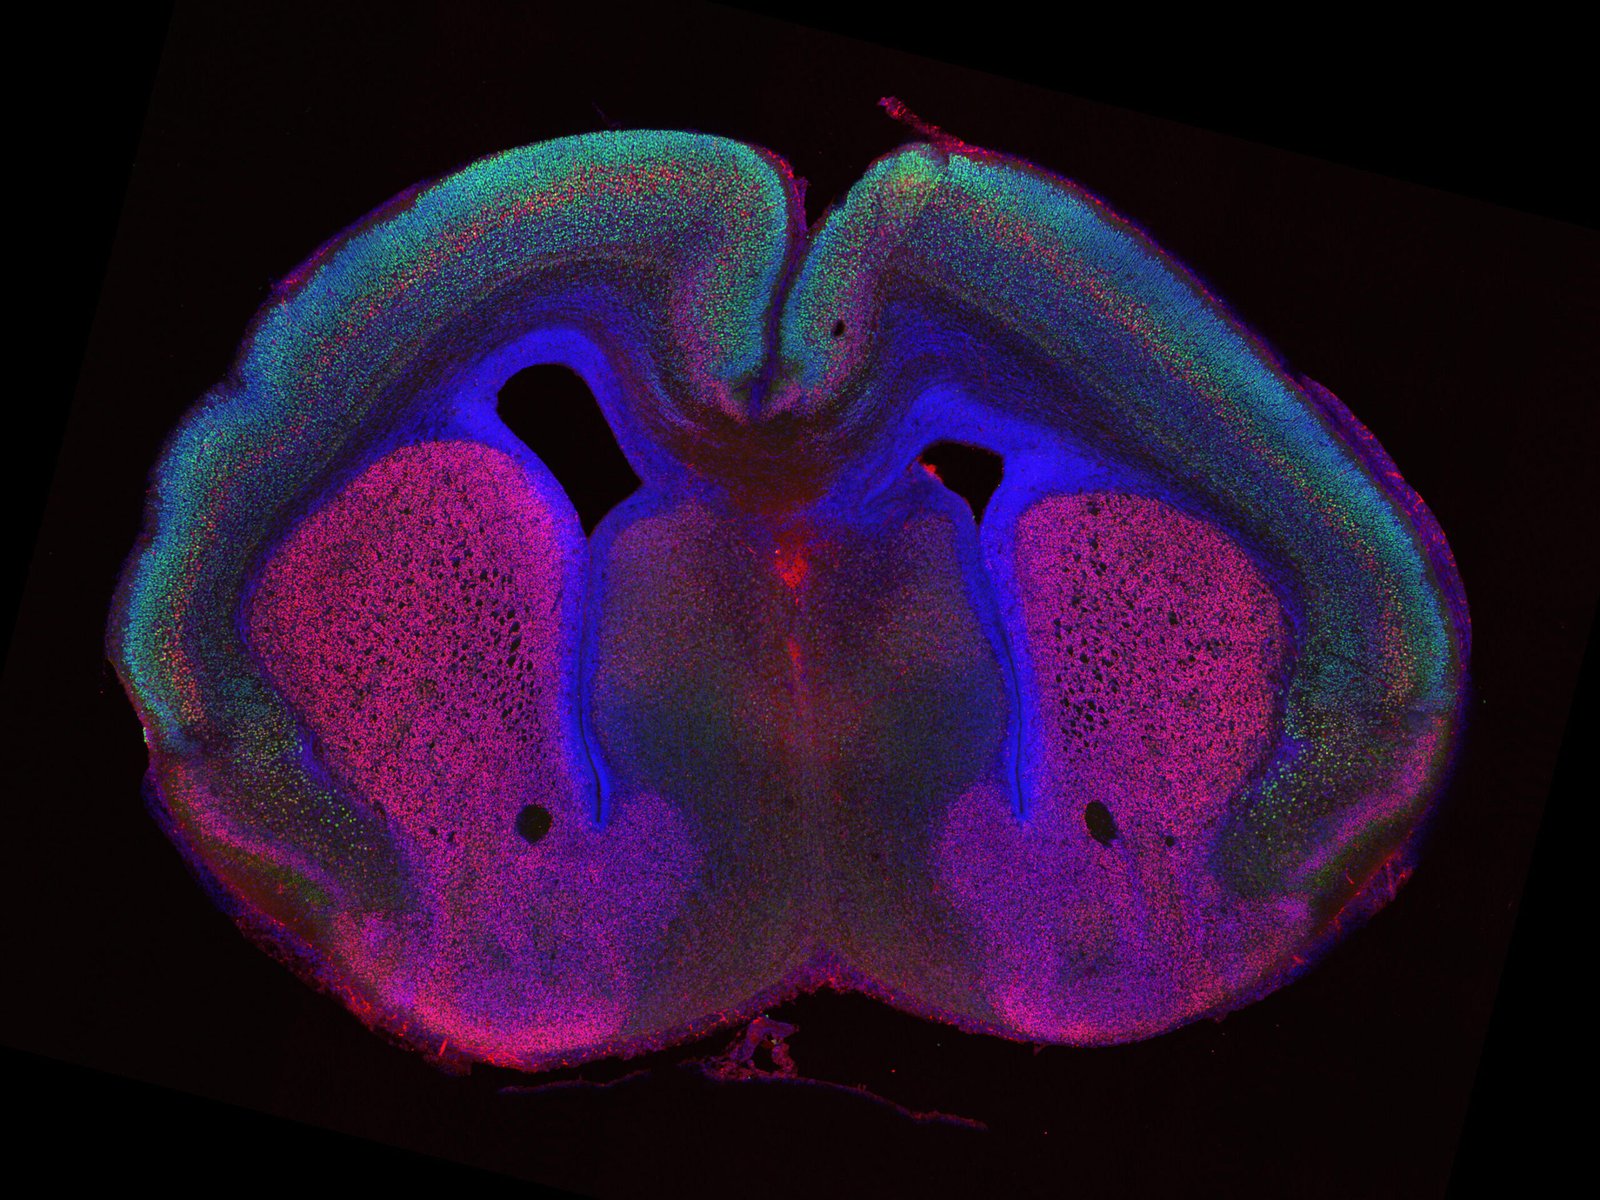

To answer this mystery, researchers at the Max Planck Institute for Biological Intelligence turned to an unlikely model—the mouse brain. Unlike humans, mice have smooth cortices, which makes them useful for studying what happens when folding begins to emerge.

Earlier work by Rüdiger Klein’s team showed that removing certain adhesion molecules—the proteins that help neurons migrate together—changed the way brain cells moved during development. Without these molecules, neurons spread out more loosely, and astonishingly, the normally smooth mouse cortex began to wrinkle, forming grooves reminiscent of the human brain.

Building on their earlier work, the researchers added another layer to the puzzle: increasing the number of progenitor cells—the early-stage cells that give rise to neurons. When they combined this boost in cell numbers with altered migration, the mouse brains developed even more pronounced folds, with strikingly complex patterns of grooves and ridges.

Through genetic tools, single-cell sequencing, and computer simulations, the team uncovered that not all progenitor cells behave the same way. For example, when intermediate progenitors were increased, sulci (grooves) formed more readily. In contrast, boosting apical progenitors favored the formation of gyri (ridges).